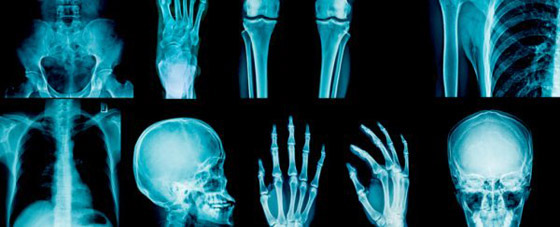

المعاناة من كسور في العظام أو حروق في الجلد، قد تبدو كنهاية العالم بالنسبة لأغلب البشر، إلا أن تلك النظرة السلبية لم تتملك يوما أسرة مارسيلي، التي لا يلاحظ أفرادها أحيانا إصاباتهم المختلفة، ببساطة لأنها عائلة لا تشعر بالألم.צبدأ الأمر عندما ذهبت إحدى أفراد أسرة مارسيلي للطبيب، وهي الجدة على وجه التحديد، حيث كانت تشكو من أزمة ظنت أنها بسيطة في عظام الكاحل، لتفاجأ بعد إجراء الأشعة أنها تعاني من كسر في تلك المنطقة ولم تشعر به، ما فتح المجال لإجراء دراسة طبية على أفراد الأسرة جميعا، بعدما اتضح كونها عائلة لا تشعر بالألم بدرجات مريبة. يتحدث د. جيمس كوكس، وهو عالم الوراثة من جامعة لندن الإنجليزية، وأحد المشاركين في الدراسة التي أجريت على أفراد أسرة مارسيلي: «لاحظنا وجود خلل وراثي لدى الأسرة، يمنع أفرادها من الشعور بالألم، لذا بحثنا على مدار سنوات عن الجين المسؤول عن تلك الظاهرة المثيرة للجدل، والتي تتفرد بها عائلة مارسيلي».

توصل الباحثون إلى أن الخلل الذي يمنع الأعصاب من الإحساس بالألم بدرجات طبيعية، يبدو ممثلا في غياب جين يدعى ZFHX2، ما تم اكتشافه من خلال فحوصات DNA حمض نووي طويلة، أجريت على أفراد الأسرة جميعا بلا استثناء، كما قام الباحثون بإزالة الجين نفسه من فئران التجارب، ليلاحظوا فيما بعد أن الفئران صاروا لا يشعرون بالألم، تماما مثلما يحدث لأسرة مارسيلي الإيطالية. يرى الأطباء والباحثون أن الظاهرة العجيبة لأسرة مارسيلي، يمكن استغلالها من أجل اكتشاف أدوية علاجية قادرة على منع الألم بشكل مؤكد لدى المرضى، ما تشير إليه الطبيبة والأستاذة بجامعة سيينا الإيطالية، آنا ماري: «مع اكتشاف سر الحالة الخاصة بأفراد أسرة مارسيلي، يمكننا التوصل يوما ما إلى علاج دوائي قادر على منع الإحساس بالألم تماما».